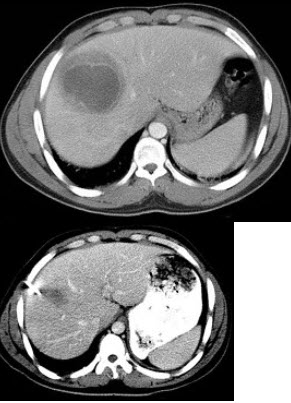

98、单项选择题

女,25岁,上腹疼痛不适,低热,有阿米巴痢疾病史,CT检查发现肝右叶低密度病变,如图,最可能的诊断是()

A.原发性肝癌

B.肝血管瘤

C.肝错构瘤

D.阿米巴肝脓肿

E.肝转移瘤